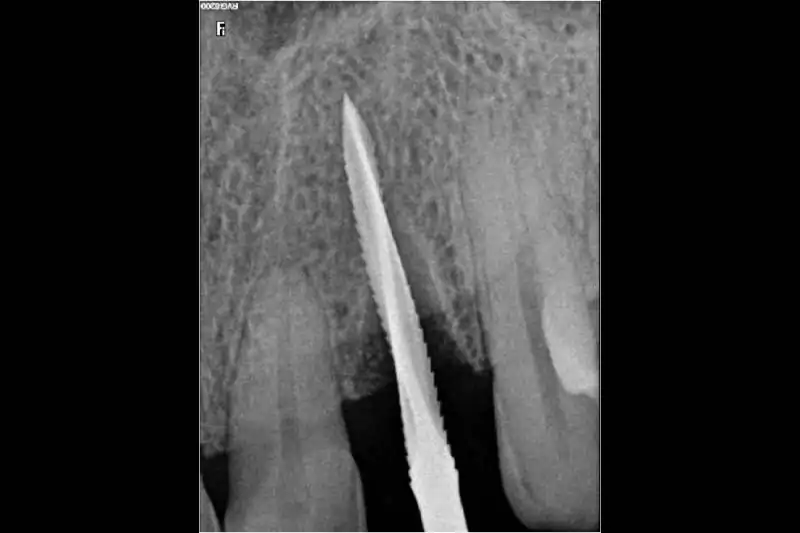

After a thorough clinical examination of your jaw bone, the Best dentist in Pune at Smilex confirms the available jaw bone by CBCT scan or X-rays. The doctors then administer a very small cut in the gums under local anesthesia. A painless drill sequence leads to the final drill position, after which the dental implants in Pune are placed in the bone. Gums are then placed back in their original position. A single implant procedure takes up to 45 mins to be done.